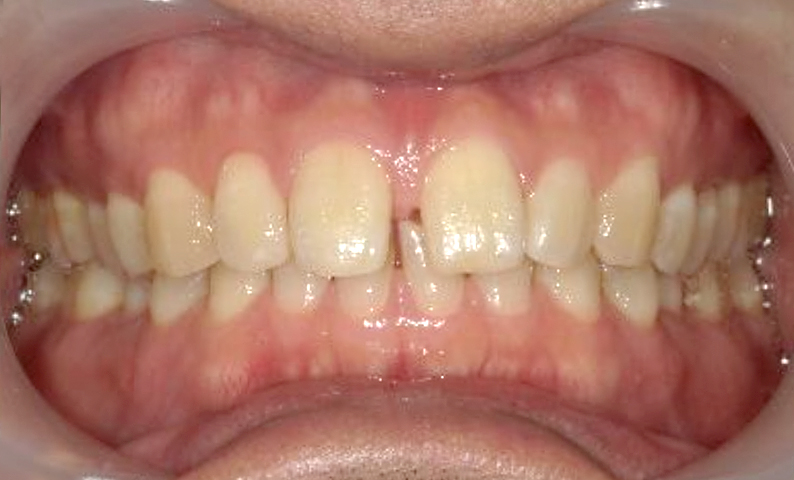

症例_001 前歯「すきっ歯」症例

治療期間:9ヶ月金額:51万円+税20代女性すきっ歯

| Before | After |

|---|---|

|